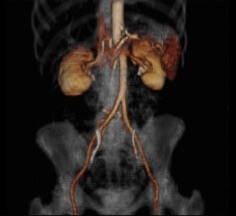

Vascular disease usually involves either narrowing of the blood supply (arteries) to the peripheral tissues often due to furring up, or an aneurysm (blow out) of the main artery: the aorta. The latter called an abdominal aortic aneurysm is catastrophic if it bursts unexpectedly with greater than 95% mortality. However, it can be safely treated if detected early enough using either an ultrasound or CT scan.